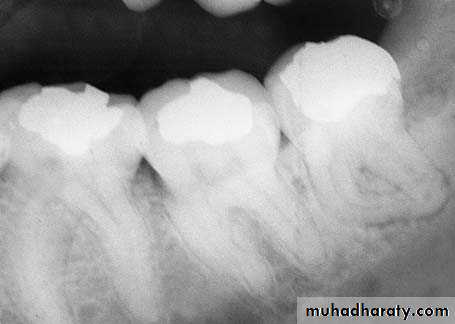

If the root or tooth is in an intimate contact to the inferior alveolar nerve, damage can be prevented or minimized only by preoperative radiographic diagnosis and surgical removal of the tooth or root.